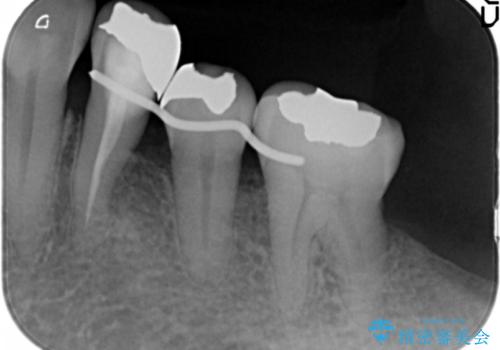

再生療法から1年後、リエントリー手術により骨の再生を確認し、骨外科処置(骨を平らにして歯周ポケットの根本的な改善を図る処置)を行いました。

再生療法と骨外科処置により、歯周ポケットは全周2mm以下となりました。